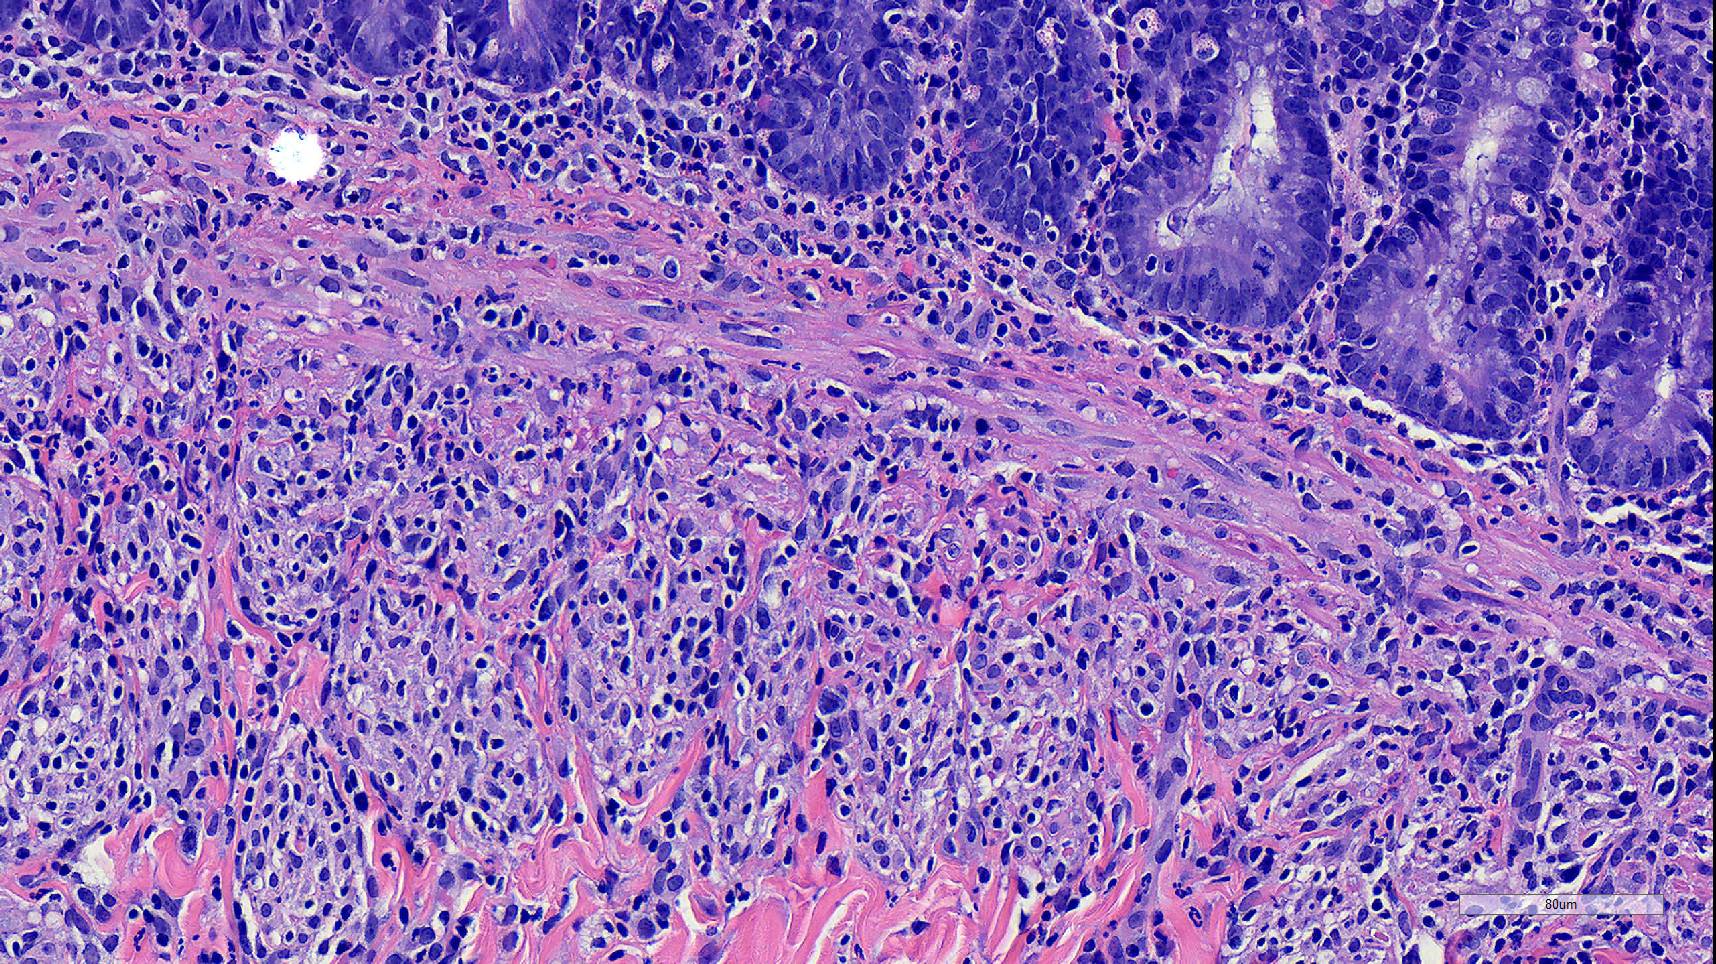

Microscopic Description:

Duodenum, jejunum and ileum: Diffusely throughout the sections, there is partial to complete loss of the leiomyocytes of the outer and inner muscularis, which are multifocally replaced by loose fibrous connective tissue (fibrosis). The remaining smooth muscle is infiltrated by large numbers small and intermediate lymphocytes, few macrophages and neutrophils. The same inflammatory infiltrate is present throughout the muscularis mucosae. Remaining leiomyocytes have pale, frequently vacuolated cytoplasm. In the submucosa, muscularis and serosa there are small to moderate numbers of perivascular lymphocytes. Small lymphocytes, and infrequently neutrophils, surround or infiltrate the myenteric and submucosal ganglia, though neurons do not exhibit degenerative changes. The lamina propria contains a markedly increased number of lymphocytes, plasma cells and a mildly increased number of eosinophils. The epithelium is diffusely overlain by myriad bacterial rods. The serosa is mildly expanded by increased clear space (edema) and is lined multifocally by markedly hypertophied mesothelium. In the stomach a similar process is observed but restricted to the outer aspect of the muscularis with a patchy/multifocal distribution and sparing of the muscularis mucosae. (section not submitted).

Duodenum, jejunum and ileum: Severe, diffuse, chronic lymphocytic leiomyositis with severe muscularis atrophy; marked, diffuse, chronic lymphoplasmacytic enteritis.

Microscopic findings reported for this condition consist of mild to marked mononuclear infiltrate, myofiber degeneration and fibroplasia or fibrosis centered within the muscularis propria of the stomach, small and large intestinal wall with the jejunum being the most severely and chronically affected segment.7,15 In early lesions the inflammation and smooth muscle degeneration are segmental, random between the outer and inner muscularis layers and sparing of the muscularis mucosae.15 Concurrent cecal involvement leading to impaction has also been described.5 Consistent histologic findings included T-lymphocyte inflammation within the muscularis propria with relative sparing of the mucosa, submucosa and neural plexuses.14 In one case report the inflammatory infiltrate was predominantly of B-lymphocytes and featured extensive angiogenesis.6 Leiomyocytes appear to be the target of the inflammation given the presence of various stages of degeneration leading to complete myofiber loss in chronic stages of the disease. Superficial inflammation is a frequent secondary finding in CIPO and has been associated with bacterial overgrowth, which were changes observed in this case.6 Neuropathy has not been a feature in most reports of canine CIPO. Inflammatory cells obscuring the myenteric and submucosal plexuses in this case were considered an extension from the neighboring inflammation as no degenerative changes were observed in the neurons. Myenteric ganglionitis has, however, been reported occurring concurrently with leiomyositis.10

Small intestine: Leiomyositis, lymphocytic, chronic, diffuse, severe, with marked smooth muscle loss and fibrosis.